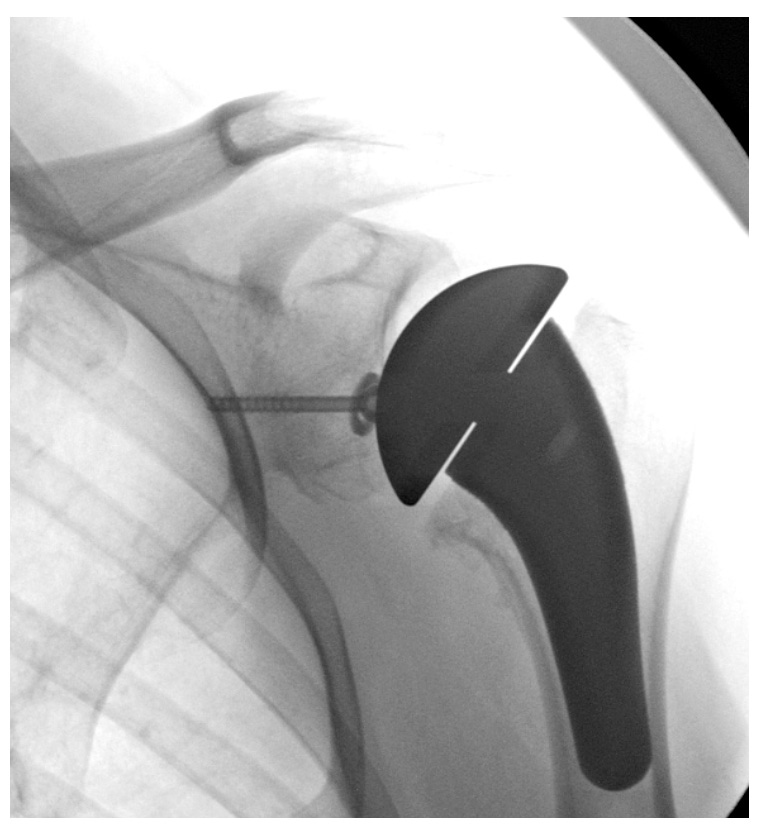

2. Total Anatomik Omuz Protezi

Omuz ekleminin tamamında kireçlenme (osteoartrit*) olan hastalarda uygulanır. Hem humerus başı hem de glenoid (yuva) yüzeyi değiştirilir. Rotator manşet tendonlarının sağlam olması gerekir; aksi takdirde protezde çıkık veya gevşeme riski artar.

Kaynak: Matsen FA, et al. *J Bone Joint Surg Am.* 2007 – Anatomik protezler sağlam manşet varlığında 10 yılın üzerinde başarıyla çalışabilir.